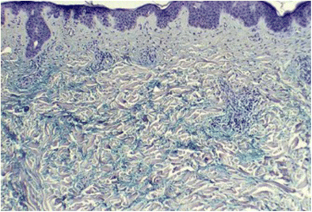

Crowson AN, Magro C (2001) The cutaneous pathology of lupus erythematosus: a review. J Cutan Pathol 28(1):1–23

Rémy-Leroux V, Léonard F, Lambert D, Wechsler J, Cribier B, Thomas P, Adamski H, Marguery MC, Aubin F, Leroy D, Bernard P (2008) Comparison of histopathologic-clinical characteristics of Jessner's lymphocytic infiltration of the skin and lupus erythematosus tumidus: multicenter study of 46 cases. J Am Acad Dermatol 58(2):217–223. doi:10.1016/j.jaad.2007.09.039

Kuhn A, Richter-Hintz D, Oslislo C, Ruzicka T, Megahed M, Lehmann P (2000) Lupus erythematosus tumidus—a neglected subset of cutaneous lupus erythematosus: report of 40 cases. Arch Dermatol 136:1033–1041

Rongioletti F, Rebora A (1991) The new cutaneous mucinoses. A review with an up-to-date classification of cutaneous mucinoses. J Am Acad Dermatol 24:265–270